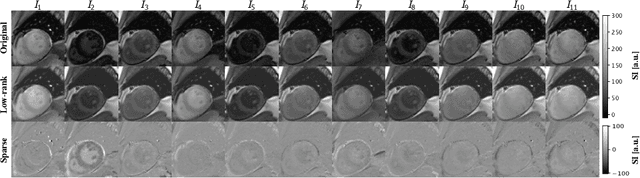

Abstract:Quantitative cardiac magnetic resonance imaging (MRI) is an increasingly important diagnostic tool for cardiovascular diseases. Yet, co-registration of all baseline images within the quantitative MRI sequence is essential for the accuracy and precision of quantitative maps. However, co-registering all baseline images from a quantitative cardiac MRI sequence remains a nontrivial task because of the simultaneous changes in intensity and contrast, in combination with cardiac and respiratory motion. To address the challenge, we propose a novel motion correction framework based on robust principle component analysis (rPCA) that decomposes quantitative cardiac MRI into low-rank and sparse components, and we integrate the groupwise CNN-based registration backbone within the rPCA framework. The low-rank component of rPCA corresponds to the quantitative mapping (i.e. limited degree of freedom in variation), while the sparse component corresponds to the residual motion, making it easier to formulate and solve the groupwise registration problem. We evaluated our proposed method on cardiac T1 mapping by the modified Look-Locker inversion recovery (MOLLI) sequence, both before and after the Gadolinium contrast agent administration. Our experiments showed that our method effectively improved registration performance over baseline methods without introducing rPCA, and reduced quantitative mapping error in both in-domain (pre-contrast MOLLI) and out-of-domain (post-contrast MOLLI) inference. The proposed rPCA framework is generic and can be integrated with other registration backbones.